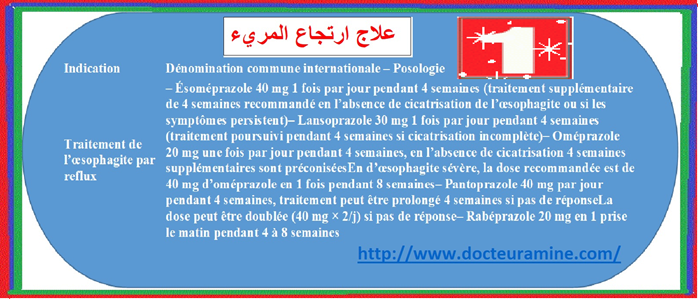

تحتل أدوية م م ب المحل الرئيسي في أخذ موقف علاج حالة الارتجاع المعدي المريئي. يبات ا م م أقل حموضة وبالتالي أقل تسمما للغشاء المخاطي المريني (13) الأمر الذي يؤول الى سرعة التئام الآفات أو جروح الالتهابات المريئية (14). بجانب تحقيق وتراجع الأعراض الناجمة عن الارتجاع المعدي المريئي يتم اللجوء الى تناول م م ب . بجانب تحقيق وتراجع اعراض الناجمة عن الارتجاعي المعدي المريئي. يتم اللجوء لتناول م م ب قصد التئام التهاب المريء الناجم عن حالة الترجيع المعدي المريئي للوقاية ضد الانتكاسات التي تبرز بعد التئام الجراح بجانب علاج حالة الجزر المعدي المريئي الذي تخلفه عقاقير ا م م البروتون التميز بالأعراض السريرية و وجود الدم في البراز. تختلف الجرعات الموصي بها حسب وجود أو عدم التهاب المريء. يلخص جدول رقم 1

ترخيصات تسويق مثبطات مضخة البروتون.

توصف م م ب جرعة كاملة (17). بينما نكتفي بأربعة أسابيع لعلاج التهاب المريء الغير شديد ومن أجل الوقاية بواسطة مم ب جرعة كاملة أو نصف الجرعة تصديا للانتكاسات